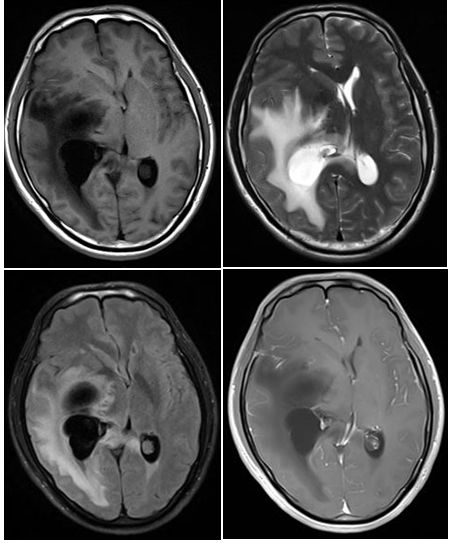

患者,25岁男性,右手电击样感觉和力弱5年。入院查体:右手大小鱼际肌无力,扬鞭征阳性。辅助检查:维生素B12浓度正常。重金属砷、汞、铅浓度正常。颈椎MRI图A、B。经颈椎前路融合术6月后患者右手活动性明显好转。复查颈椎MRI见图C。

答案:平山病

颈椎MRI常规扫描T2WI示颈椎C4-C6椎体水平颈髓形态变细,其内可见纵行长T2信号影,在过屈位(flexional position)磁共振,可以清楚地看到下颈后部硬膜之往前位移而压迫到颈髓。上述是平山病影像特点。平山病是一种少见的局灶性缺血性颈脊髓灰质病,其确切的发病率和患病率不清。主要影响青少年男性,被认为是由颈髓腹侧运动神经元的动态机械损伤或缺血性损伤引起。1959年由Hirayama首先报道。常隐袭起病,表现为一侧手部肌肉的无力和萎缩,肌萎缩局限在手和前臂肌肉,多单侧受累,常无脑神经症状,无锥体束征,无大小便障碍。颈部过屈位MRI扫描多可明确诊断。